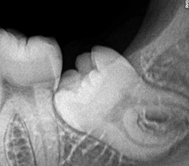

Impacted Teeth

Tooth cannot erupt due to physical barrier,

Teeth impacted again other teeth or within jaw where more chances of cyst.

હાડકા ની અંદર રહેલો દાંત

હાડકાની અંદર રહેલો દાંત ઘણી વાર બહાર આવી શકતો નથી અને તે અમુક સંજોગોમાં જડ બા માં ગાંઠ કરી શકે